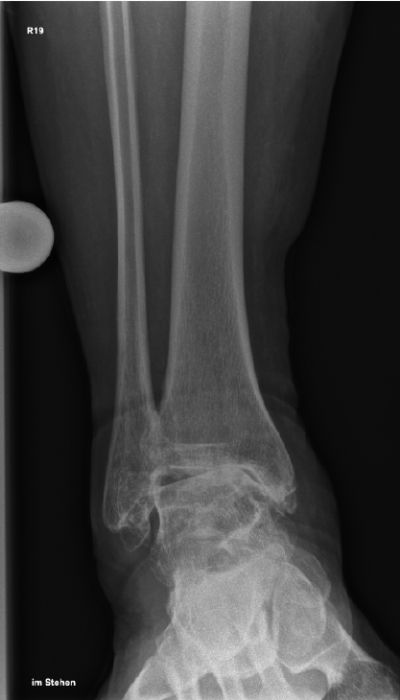

Eine ausführliche Anamnese und körperliche Untersuchung ist der Grundstein der Diagnostik und meistens bereits richtungsweisend. Typisch sind Schmerzen, Schwellung, Instabilität, Belastungseinschränkung sowie eine verminderte Beweglichkeit im oberen Sprunggelenk. In der klinischen Untersuchung sollte auf lokalen Druckschmerz, Bandinstabilitäten und Achsfehlstellungen geachtet und simultan die Funktion bzw. Beschwerden in den Nachbargelenken erfasst werden. Die Röntgen-Bildgebung sollte unter Belastung der betroffenen Extremität durchgeführt werden. Insbesondere der Mortise-view (Abbildung a) und die seitliche Aufnahme (Abbildung b) ermöglicht eine gute Beurteilung der Gelenksituation. Eine Ganzbeinaufnahme sollte erwogen werden, um statische Ursachen wie zum Beispiel kniegelenksnahe Achsdeformitäten zu detektieren. Bei Achsfehlstellungen, welche auf einer Rückfußproblematik basieren, ist der Hindfoot-View ein wichtiges diagnostisches Hilfsmittel. Bestehen ligamentäre Instabilitäten, eine unklare Situation der Nachbargelenke oder anzunehmende degenerative Sehnenveränderungen, kann eine MRT zur weiteren Therapieplanung sinnvoll sein (6). Bei komplexen knöchernen Situationen, insbesondere nach Frakturen mit eventuell vorhandenen Implantaten, kann die Computertomografie (CT) die Diagnostik sinnvoll erweitern. In ausgewählten Fällen kann die Arthroskopie zur Festlegung der geeigneten Behandlungsstrategie herangezogen werden. Zunehmend kommen ergänzende bildgebende Verfahren wie die „weight-bearing-CT“ zum Einsatz. Im klinischen Alltag ist der Stellenwert noch gering. Jedoch wird im Zuge der vermehrt durchgeführten präoperativen 3D-Planung eine wachsende Bedeutung erwartet (7).

Röntgenaufnahme des rechten Sprunggelenks im seitlichen Standbild zur medizinischen Untersuchung.

Abbildung a-d: 78-jähriger Patient mit viertgradiger OSG-Arthrose bei varischer Verkippung des Talus. Verlaufskontrolle 6 Wochen nach Implantation der OSG-TEP. Noch erkennbare Bohrlöcher in der Tibia von der Ausrichtungslehre der OSG-TEP.

Der Patient, 78 J., männlich, stellte sich mit seit Jahren bestehenden, progredienten Schmerzen im rechten OSG in der Sprechstunde vor. Klinisch zeigte sich eine plantigrade Fußstellung bei varischer Rückfußachse. Die Beweglichkeit war eingeschränkt, Dorsal-/Plantarflexion OSG rechts 0/0/35°. Motorik, Durchblutung und Sensibilität waren intakt. Im Röntgen wurde eine viertgradige OSG-Arthrose bei ausgeprägter varischer Verkippung des Talus und Synostose des distalen Tibiofibulargelenkes deutlich. Nach Ausschöpfung der konservativen Therapiemaßnahmen stellten wir die Indikation zur Implantation einer OSG-TEP mit ergänzender minimalinvasiver Umstellungs­osteotomie des Calcaneus. Postoperativ erfolgte die Mobilisation im langen Walker mit Bodenkontaktlauf. 6 Wochen postoperativ lagen reizlose Narbenverhältnisse vor. Das Bewegungsausmaß stellte sich mit Dorsal-/Plantarflexion 10°/0°/40° verbessert dar. Es bestand noch eine moderate Schwellneigung. Im Röntgen zeigte sich eine gut integrierte OSG-Endoprothese bei unveränderter Implantatlage und knöchern fusionierter Calcaneus-Osteotomie. Von Seiten des Patienten bestand eine deutliche Reduktion der Schmerzen und subjektive Zufriedenheit. Anschließend erfolgte eine rasche Steigerung der Belastung bis zur Vollbelastung ohne Walker und Gehstützen.